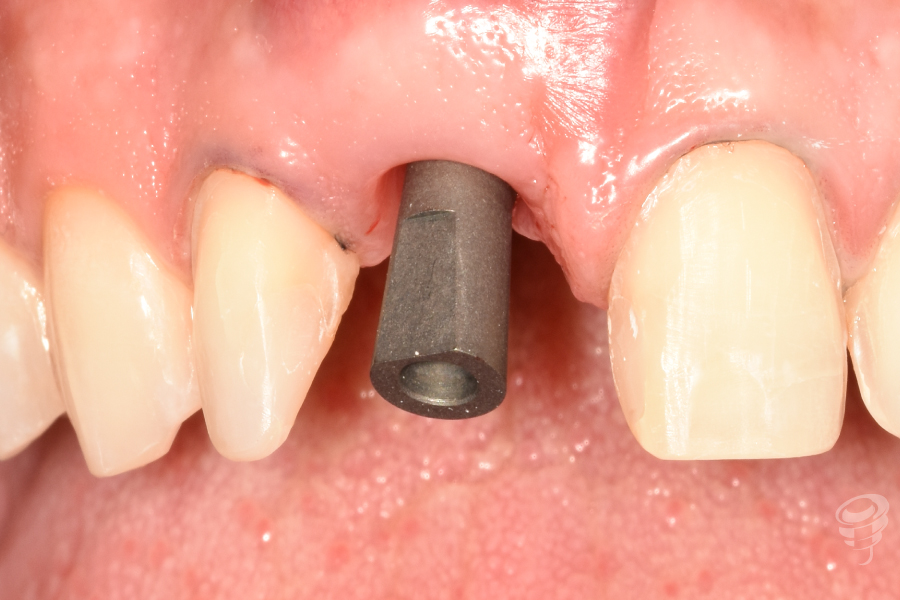

Fase 2: Controles y Segunda Etapa (Mes 4)

- Confirmación de osteointegración (ISQ > 70).

Figura 26

Figura 27

Figura 28

Figura 29